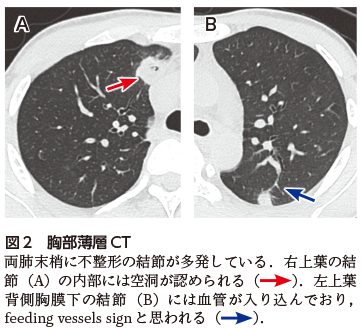

敗血症性肺塞栓症は,細菌などの病原体が血行性に散布され,肺に塞栓をきたした状態で局所に膿瘍を形成する.原因となる塞栓子は,菌塊や感染性の静脈血栓が大部分である.感染源としては右心系感染性心内膜炎が多く,敗血症や血栓性静脈炎,カテーテル関連の感染,歯科や外科処置後などでもみられる.症状は発熱,呼吸不全,血痰,胸痛などであるが,自覚症状に乏しいこともある.敗血症性肺塞栓症の診断には画像診断が有用で,胸部単純X線写真では両側多発性に結節影や限局性浸潤影,CTでは末梢胸膜下に辺縁不整な結節を認め,さまざまな程度で空洞化する(図2A).結節には血管が連続する所見がみられることもあり,feeding vessel signと呼ばれる(図2B).胸水を伴うことが多い.